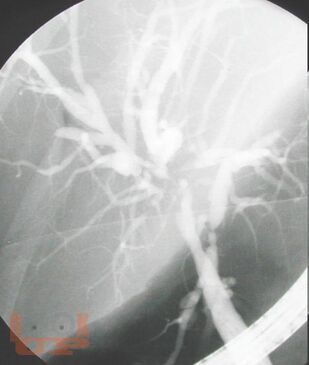

Неотложная хирургия - одно из наиболее актуальных, сложных и ответственных направлений хирургии. Пациенты пожилого и старческого возраста с механической желтухой различной этиологии толстой кишки составляют значительный контингент, госпитализируемый в хирургические стационары по экстренным показаниям. Издание реализовано с учетом опыта сотрудников кафедры и современных представлений о патогенезе, методах эндоскопической диагностики, клинических проявлениях и основных принципах лечения больных синдромом механической желтухи, обусловленной осложнениями патологии гепатопанкреатодуоденальной зоны и желудочно-кишечного тракта. Успех в лечении таких пациентов во многом зависит от своевременности и точности постановки диагноза.